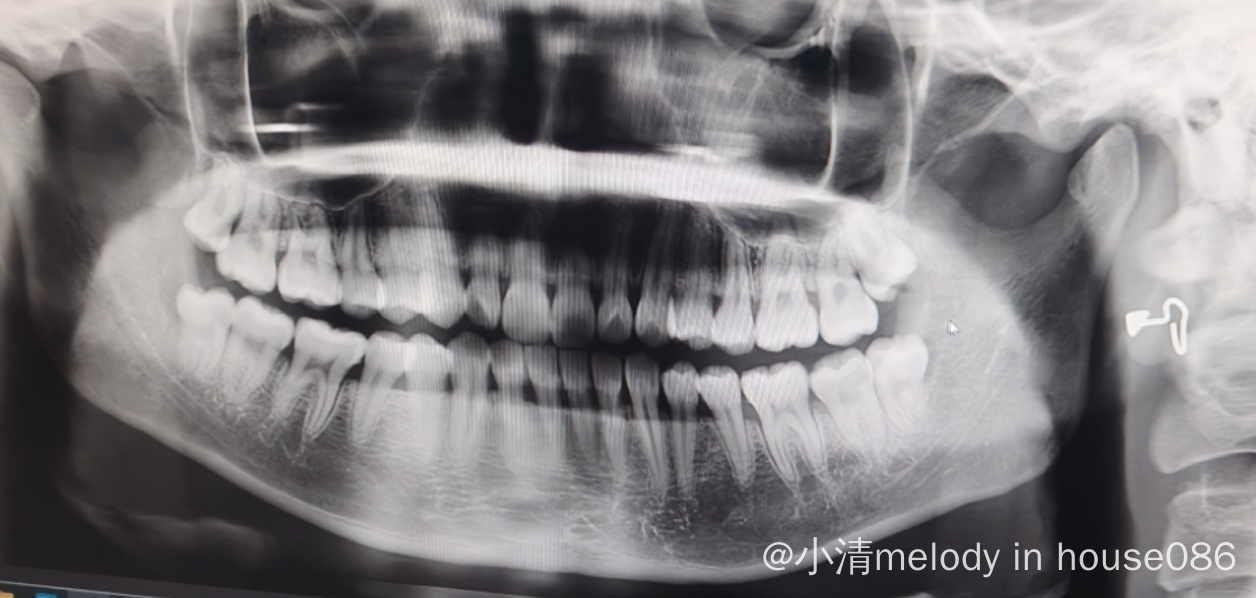

牙片如下。长得算是正常,但是医生说要用锤子锤……拔完两颗智齿(左下和右下,不在同一侧)休息十天能进舱吗 还是不要拔呢

为什么要拔牙?你这智齿看上去都长出来了呀,难道有发炎等现象吗?我刚拔了一颗牙,牙医说内部骨骼啥的长好最少三个月

一直在发炎 今天在拍片子的时候也还是在发炎 我一疗的时候发炎整个神经痛 挂了两个礼拜消炎药➕打甲硝唑